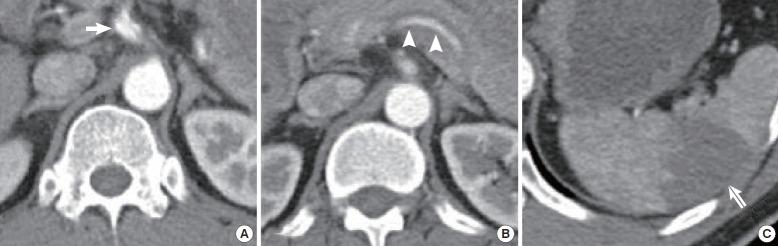

Spontaneous dissection of celiac trunk with concurrent splenic artery dissection.

Isolated spontaneous dissection of the celiac trunk is rarely diagnosed in acute abdominal pain. We present two cases of celiac trunk and splenic artery dissection with splenic infarction. Patients were successfully managed and stabilized by medical treatment. Isolated celiac trunk dissection can be fatal, therefore providers should be careful not to overlook this entity.